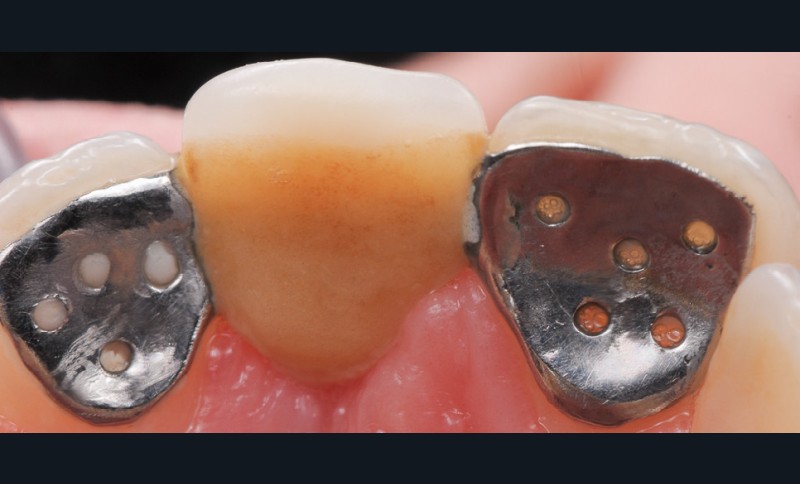

La demande du patient âgé de 20 ans au moment de cette première consultation portait sur la réfection de son bridge collé de type Rochette remplaçant sa 21. Nous avons indiqué dans cette situation clinique la réalisation d’un autre bridge collé, mais de type cantilever en céramique pour tous les avantages qu’ils possèdent.

1/ Qu’anticipez-vous dans le cas de la réfection de ce bridge collé de type Rochette (fig. 1 à 5) ?